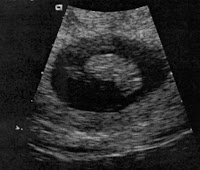

My Beautiful Cause For Nausea

(My second son, taken in 2007)